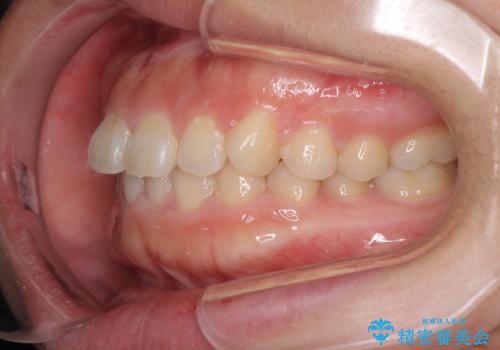

- 前歯のデコボコを治したいとのことで来院された患者様です。

上下顎ともに歯列全体の側方拡大とIPR(歯と歯の間を削る)によってデコボコが解消するように設計し、インビザラインにより治療を行うこととしました。

後方移動に際し、残っていた上顎の親知らずを抜歯することとしました。

1日22時間の装着時間をしっかり守ってくださったので、1年程度で治療を終えることができました。

1セットのマウスピースで概ね治療を終えたのですが、前歯僅かな叢生が残ったため、2セット目のマウスピースで仕上げました。

気にしていた口元の印象が改善され、患者様には大変満足していただきました。